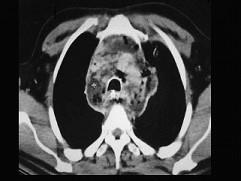

问题 男,64岁,患糖尿病,最近三天出现发热,伴颈静脉显露,结合CT图像,选择最可能的诊断 ( )

选项 A、恶性畸胎瘤 B、纵隔脓肿 C、纵隔淋巴瘤 D、侵袭性胸腺瘤 E、坏死性纵隔炎

答案 E